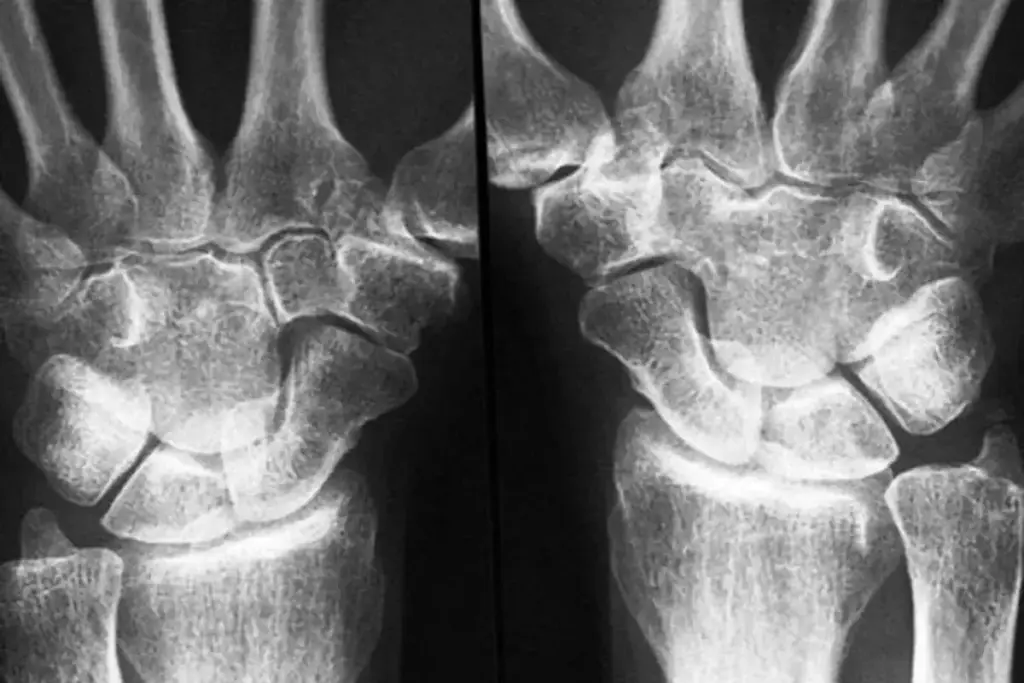

RF results must be considered alongside symptoms, imaging, and other tests to accurately diagnose or manage disease.